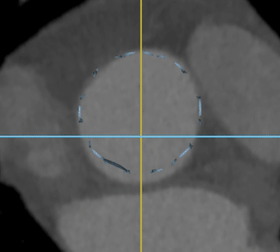

原生瓣叶被支撑臂推开之后,其上缘高度比无支撑臂瓣膜支架低约1mm,有翻边形态,与传统无支撑臂结构瓣膜支架对比,如图4-5:

图4 支撑臂植入后原生瓣叶翻边形态

图5 无支撑臂原生瓣叶腰部结构

翻边径向扩张不足1 mm,由于支架主体的收腰设计,原生瓣叶翻边形成的类圆几何形状与瓣环直径相近。同时,由于降低了原生瓣叶推开至瓣窦内的高度,增加了原生瓣叶、瓣窦与窦管交接形成的“月牙状”冠脉灌注血流通道面积,从而扩大了低冠脉开口的适应症范围。